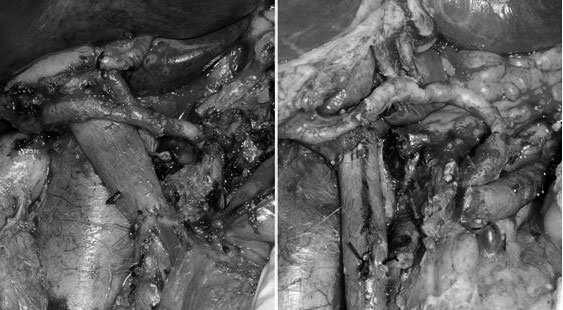

陈汝福教授国际首创了“联合胰周神经清扫的胰腺癌根治手术”。胰腺癌具有嗜神经性,常沿着神经束转移,超过90%的胰腺癌术后病理检测显示神经侵犯阳性,这是胰腺癌复发和转移的主要原因。联合神经清扫能够彻底清除胰腺周围的神经组织,最大程度地去除潜在转移的肿瘤细胞,从而提高手术的根治性效果。

联合神经淋巴清扫的胰腺癌根治术